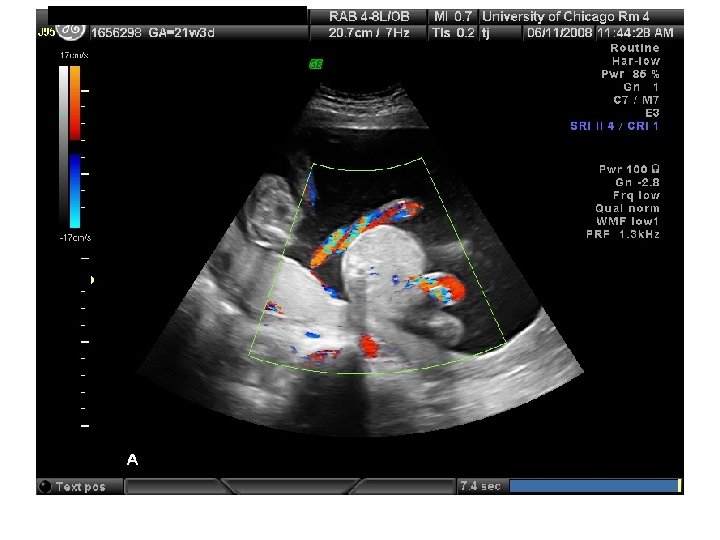

QUIZ What is Your Diagnosis? Case: Patient J. F. 30 years old, at 32 week gestation. Presented with the following pictures.

Answer: a) Trisomy 21 b) Non-immune Hydops c) Paravo virus Infection